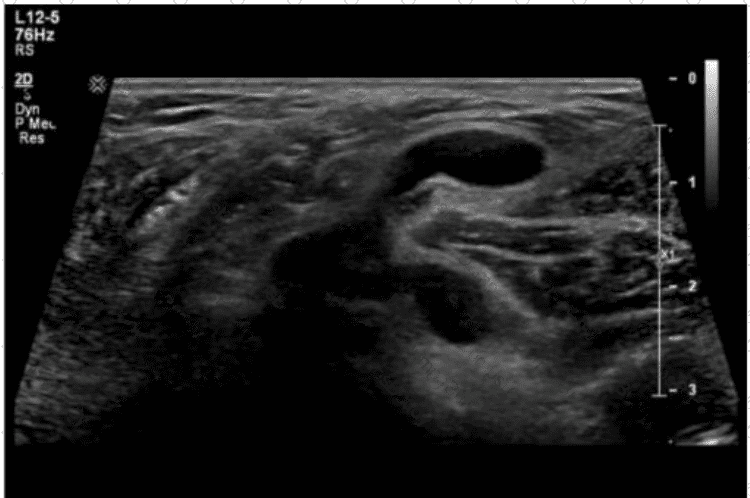

Which structure is most likely shown in this image of the right lower quadrant?